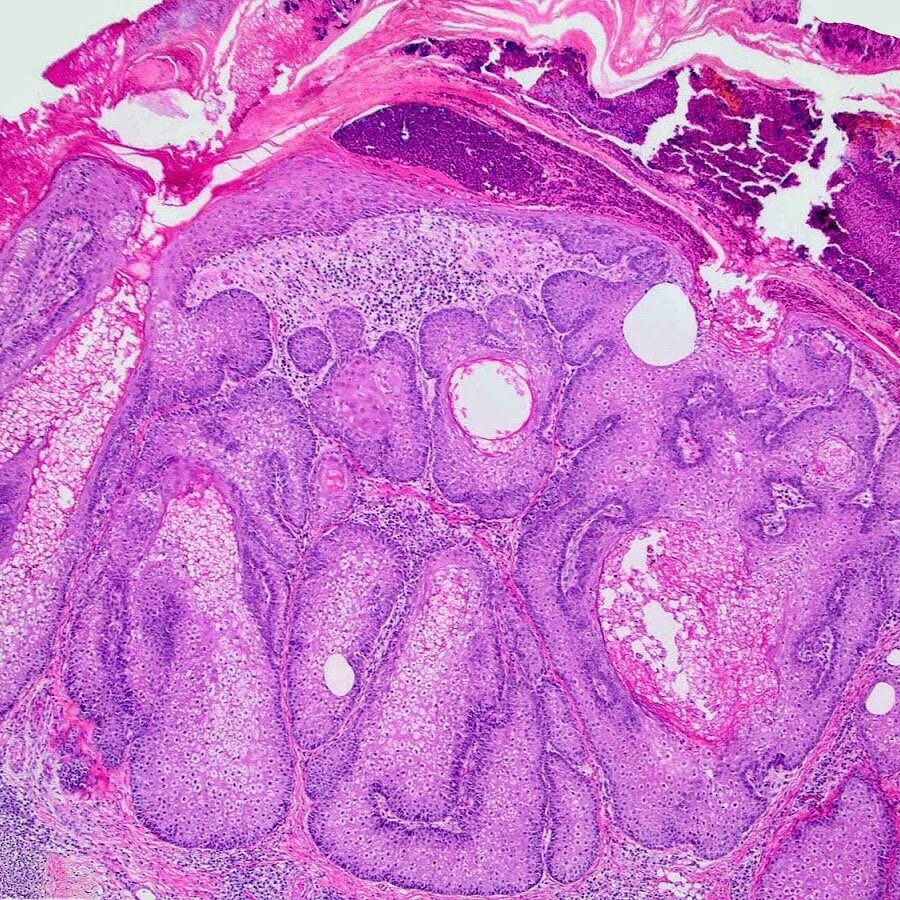

Курс гистологии начинается с цитологии, она знакома всем со школы, только изучается более глубоко. Затем студенты учат тему «эпителий», затем «соединительные ткани», «мышечные ткани», «нервные ткани», «эндокринная система», «дыхательная система», «пищеварительная система», «выделительная система», «половая система» «Кожа» и эмбриология. Конечно каждая тема по-своему сложна и интересна, но, опросив одногруппников я пришёл к выводу, что у нас единогласное решение по поводу самой сложной темы. Это половая система. Помимо строения органов, надо выучить строение всех фолликулов, овариально-менструальный цикл, возрастные особенности и много чего ещё, к тому же эта тема идёт чуть ли не последне, а значит времени ее выучить к экзамену меньше, чем у других. 😘

Это половая система. Помимо строения органов, надо выучить строение всех фолликулов, овариально-менструальный цикл, возрастные особенности и много чего ещё, к тому же эта тема идёт чуть ли не последне, а значит времени ее выучить к экзамену меньше, чем у других.